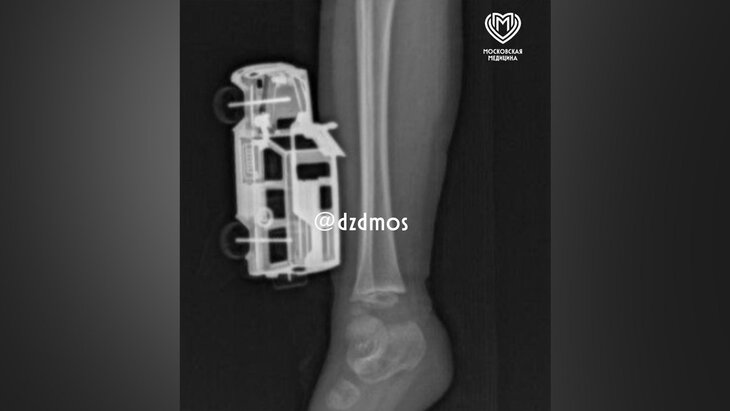

Фото: телеграм-канал "Московская медицина"

Врачи в Москве спасли 4-летнего ребенка, у которого в ноге застряла металлическая игрушечная машинка в голени, рассказали в телеграм-канале Депздрава столицы.

По словам родителей, ребенок прыгнул с кровати и неудачно приземлился на игрушку. Она повредила мягкие ткани правой голени, а части игрушки вошли до подкожножировой клетчатки. Родители вызвали скорую помощь, и ребенка госпитализировали в больницу Сперанского.

Травматолог-ортопед отделения экстренной хирургической помощи Магомед Шихахмедов рассказал, что мальчику сделали рентгенографию, так как нужно было исключить повреждения костей и понять, насколько глубокие повреждения.